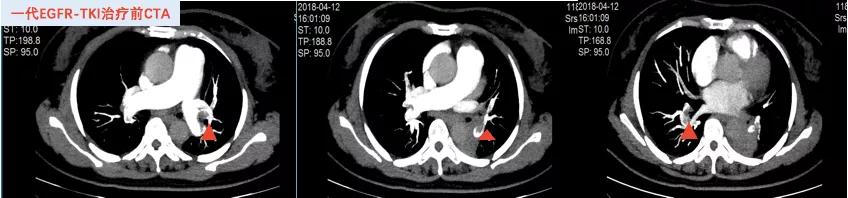

2018年4月20日开始口服“吉非替尼250mg qd”靶向治疗至2019年2月27日,疗效评价SD,PFS约10月。(图4、5)

图4 吉非替尼治疗前CTA

图5 吉非替尼治疗期间CT影像